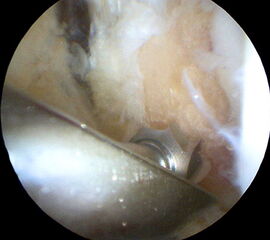

Operationstechnik

Nachfolgend wird die OP-Technik an einem rechten Sprunggelenk unter Verwendung von PEEK-Ankern veranschaulicht.